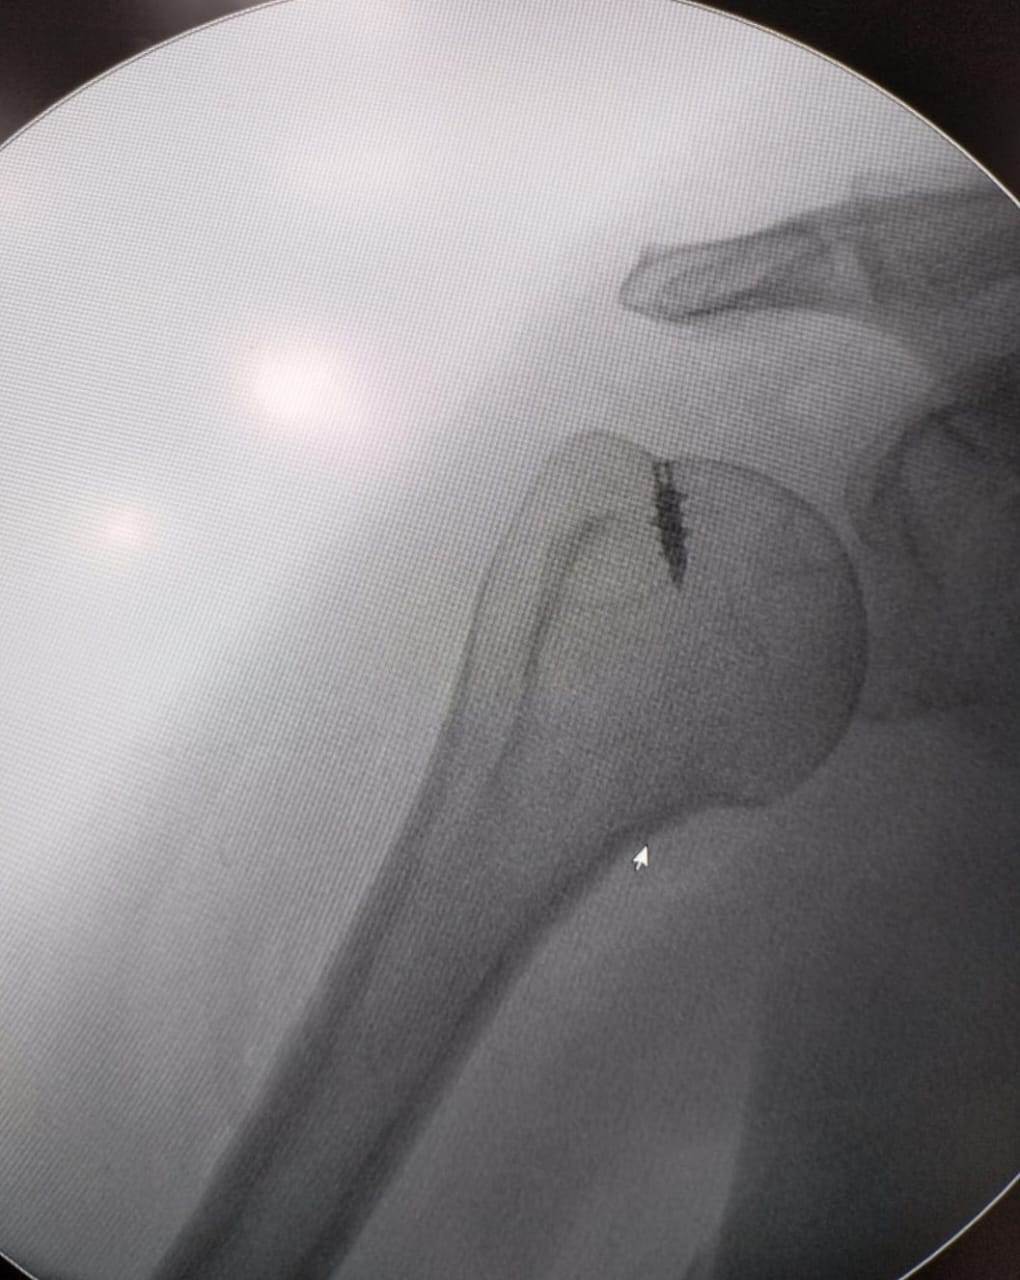

مشيرًا الى أن ذلك النوع من الكسور يكون قريبًا جدًا من الأعصاب والأوعية الدموية الرئيسية للساق والتي توجد خلف مفصل الركبة.. حيث تم الوصول الى الكسر وإعادة بناء سطح المفصل وتثبيته باستخدام شريحة ومسامير وأسلاك معدنية باستخدام جرح ٧ سنتيمترات خلف الركبة واستخدام مسامير جانبية مجوفة بدون فتح لتثبيت الجزء الخارجى من سطح المفصل، وتم الاطمئنان على الأوعية الدموية قبل إفاقة المريض، وبعد تمام الإفاقة.. تم الاطمئنان على الأعصاب والأوعية للمريض.

وأضاف أنه نظرًا لقرب هذا الكسر من سطح المفصل تم عمل أشعة مقطعية بعد الجراحة للتأكد من جودة بناء المفصل وعدم وجود أى بروز للمسامير داخل المفصل، وجارٍ تحضير المريض لعمل رنين مغناطيسى لتحديد الأربطة الداخلية والخارجية للركبة التي ستحتاج لإعادة بناء بالمنظار.